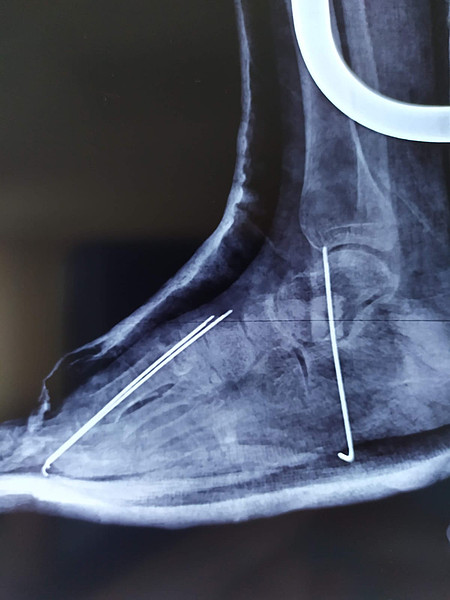

IMG_4695IMG-20230901-WA0003ДЦП_1ДЦП_2_> > >

IMG-20230901-WA0003.